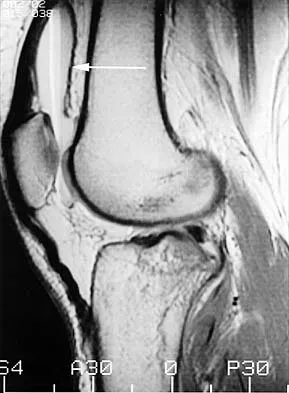

Following an acute dislocation of the patella, the risk of a recurrent dislocation is greater if the patient has which of the following findings?

Recurrent dislocations may follow an earlier dislocation. One study found that in patients who had a patellar dislocation between the ages of 11 to 14 years, 60% had a recurrent dislocation. The incidence of recurrent dislocation dropped to 33% in patients who had a patellar dislocation between the ages of 15 to 18 years. The authors also found that the incidence of recurrence was greater in patients who demonstrated a predisposition to dislocation as determined by evaluation of the unaffected knee. Predisposing signs included passive lateral hypermobility of the patella, a dysplastic distal third of the vastus medialis obliquis muscle, and a high and/or lateral position of the patella. A second study found that the risk of redislocation was considerably higher in patients who were in their teens at the first episode of dislocation compared to older patients. There are no studies linking either a patella baja or a bipartite patella to an increased risk of redislocation. Cash JD, Hughston JC: Treatment of acute patellar dislocation. Am J Sports Med 1988;16:244-249.